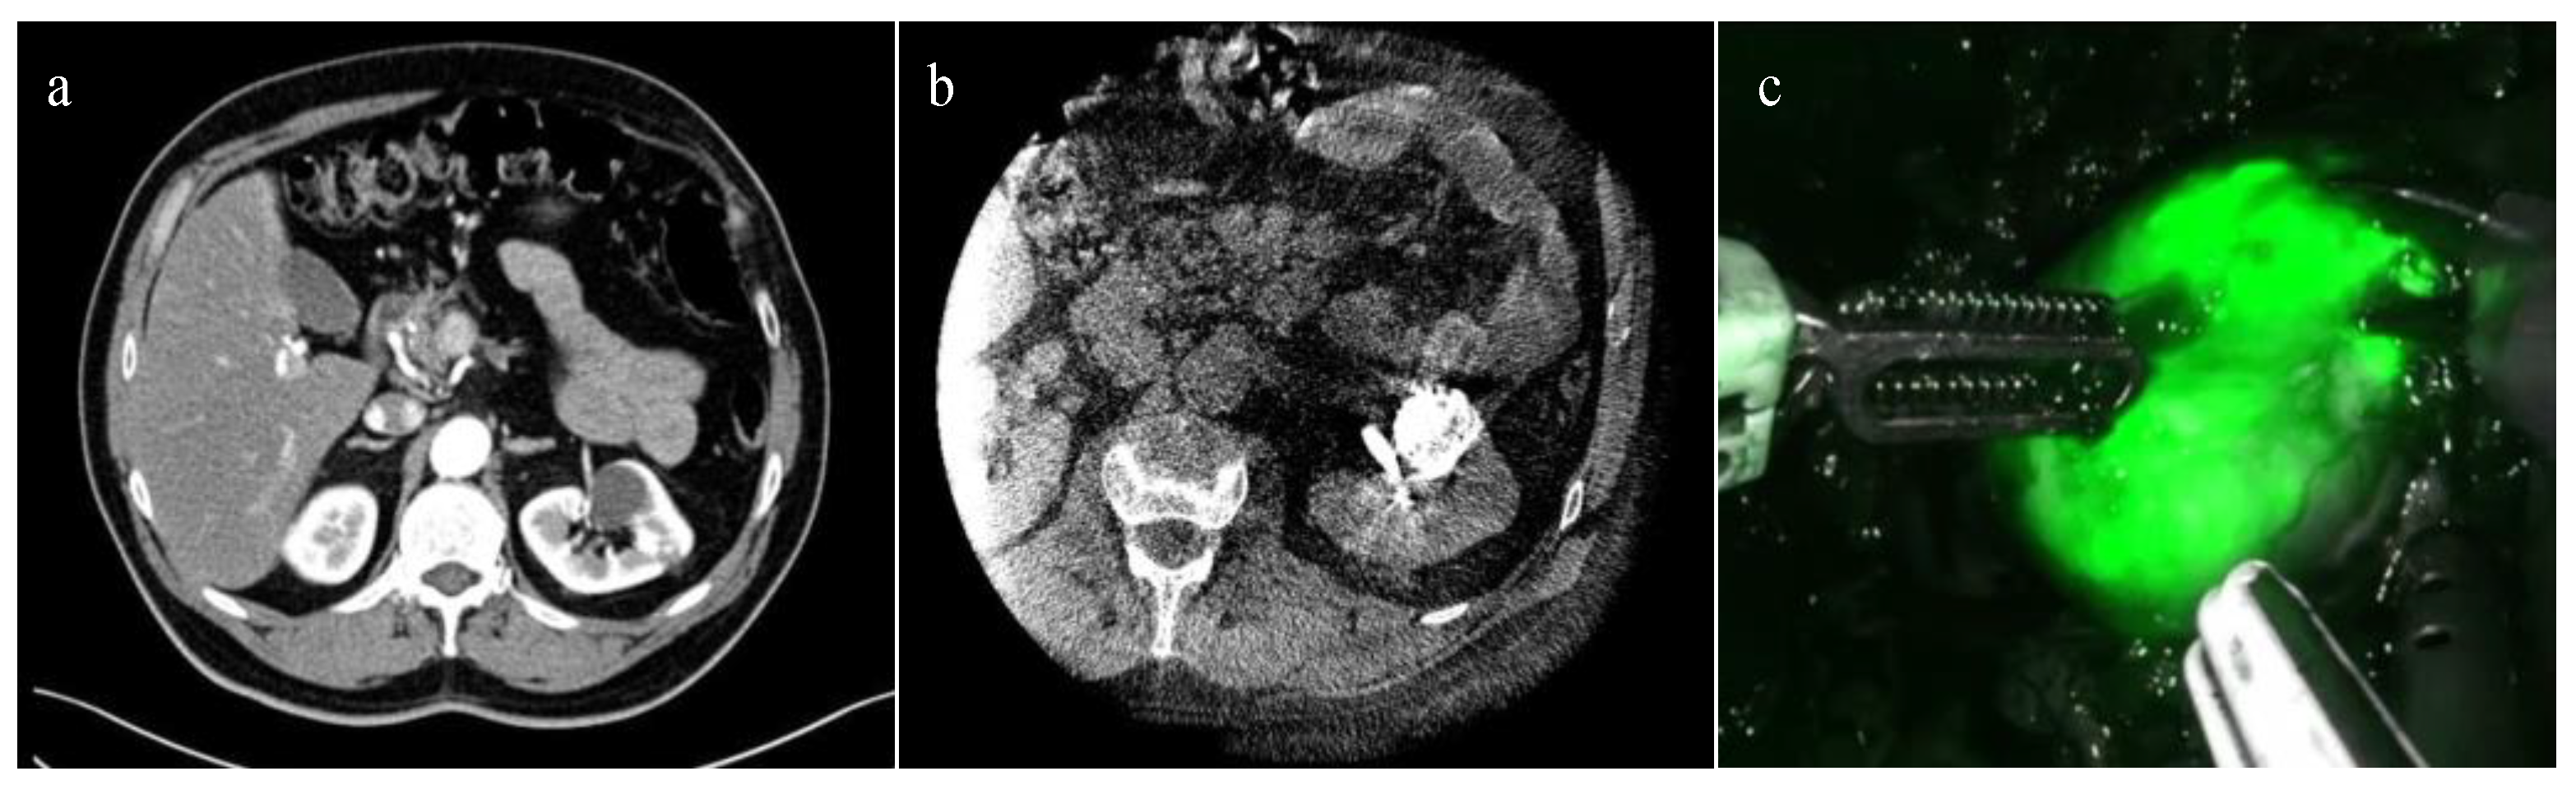

In 2022, Nardis and colleagues evaluated the clinical impact of ICG combined with Lipiodol in the context of trans-arterial super selective embolization (Figure 1), in a cohort of 41 patients with totally endophytic masses [39]. The study reported a procedure success rate of 100%, and 63.4% of the tumors were considered “visible with well-defined margins” intra-operatively. Combining ICG with other emerging technological tools for preoperative surgical strategies, such as three-dimensional (3D) reconstructions, may further enhance the potential of RAPN. An example of this application was illustrated in a pilot study by Amparore et al. published in 2023 [40], where ICG was used to overlay a 3D virtual model of the kidney onto the real organ during surgery, with promising preliminary results.

Figure 1.

ICG-guided Management of Endophytic Renal Tumors: (a) CT-scan showing a totally endophytic left renal tumor; (b) trans-arterial super selective embolization “tagging” with ICG-Lipiodol; and (c) renal tumor intraoperative ICG near-infrared imaging identification.